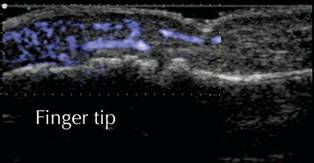

Ultrasound image of inflammation in a finger

tip